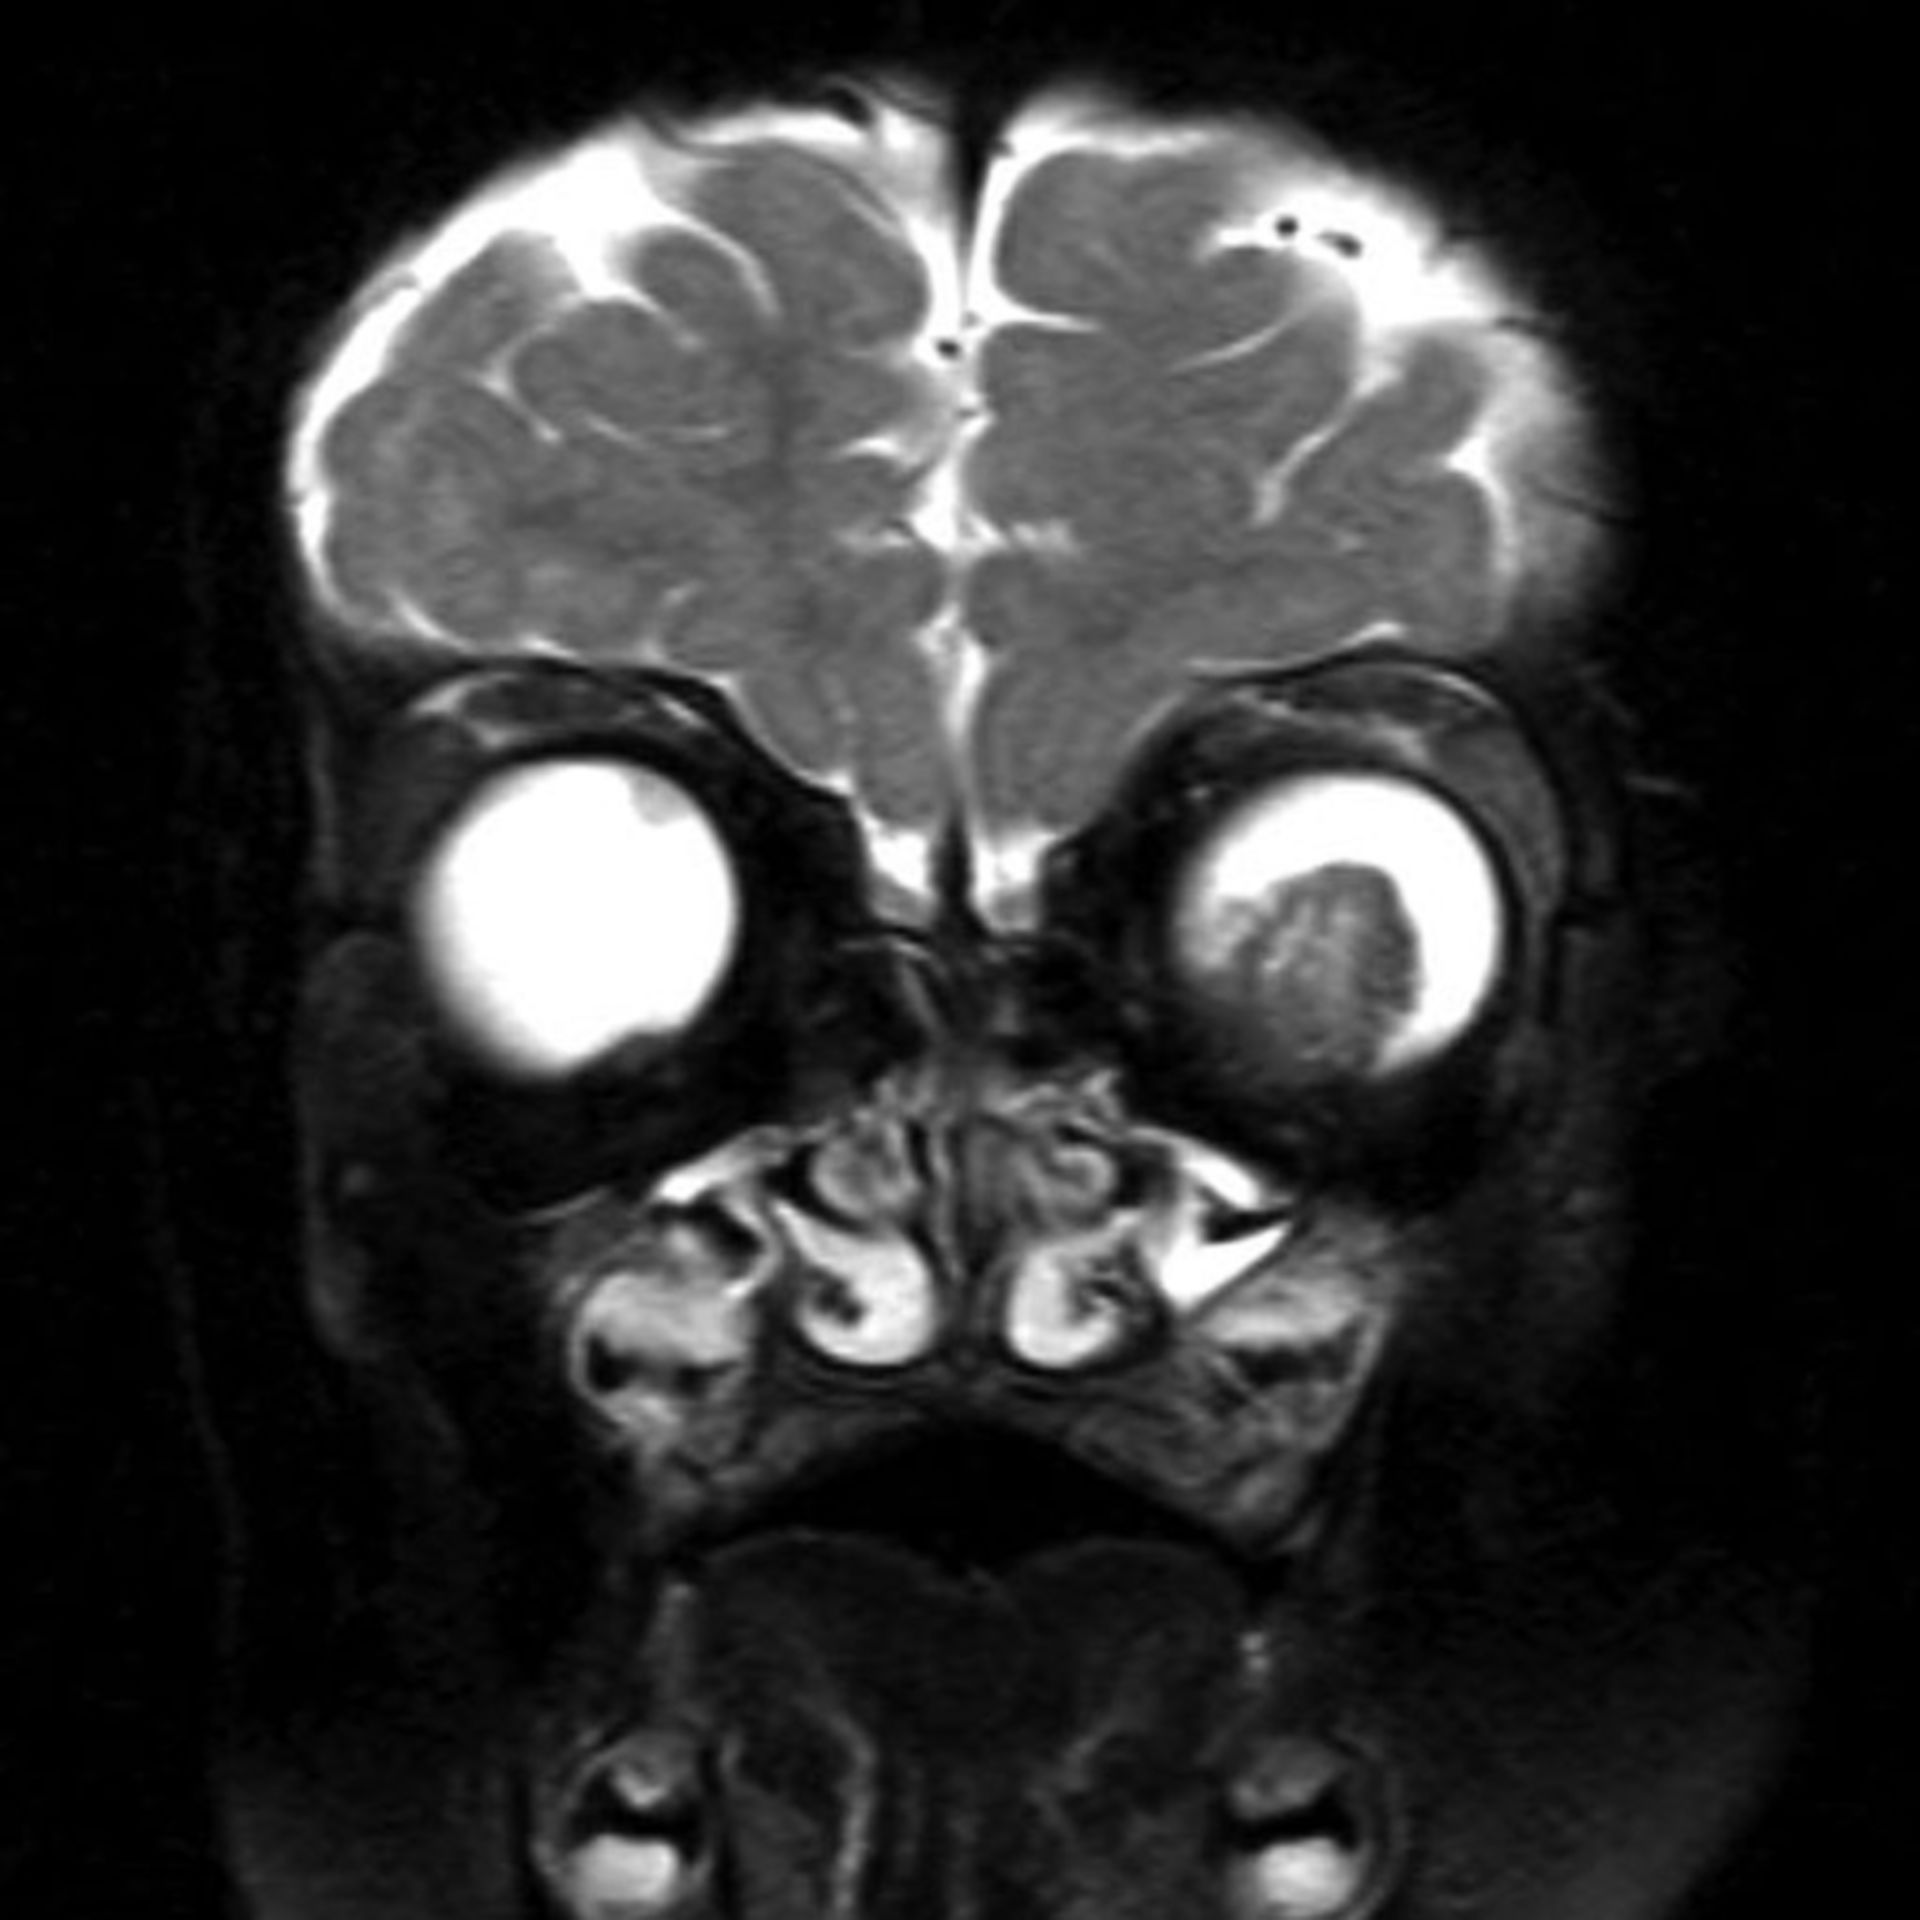

Mrt : Kuala Lumpur’s New MRT Map Alignment. ~ .: Property … / Support more model(qualcomm and … Retinoblastom (MRT/T2) – DocCheck

Retinoblastom (MRT/T1) – DocCheck (11/26) MRT Schädel in Transversalebene, T₁‐gewichtet, FFE – DocCheck

Retinoblastom (MRT/T2) – DocCheck MRT: Posterior-Hirninfarkt – DocCheck